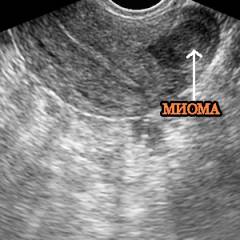

- Внутриполостная и субсерозная миома. Доброкачественная опухоль, нарушающая функционирование матки и вызывающая бесплодие, кровотечения и боли. Миома распространена, особенно у женщин в период климакса, из-за гормональных изменений. У молодых женщин встречается реже.

- Лейомиома (миома матки). Наиболее распространенная доброкачественная опухоль, встречающаяся почти у четверти женщин детородного возраста. При УЗИ выявляется увеличение матки и изменение ее контура.

- Лейомиома (миома матки). Наиболее распространенная доброкачественная опухоль, встречающаяся у четверти женщин детородного возраста. Представляет собой разросшуюся гладкомышечную ткань. На УЗИ наблюдается увеличение матки и изменение ее контура.